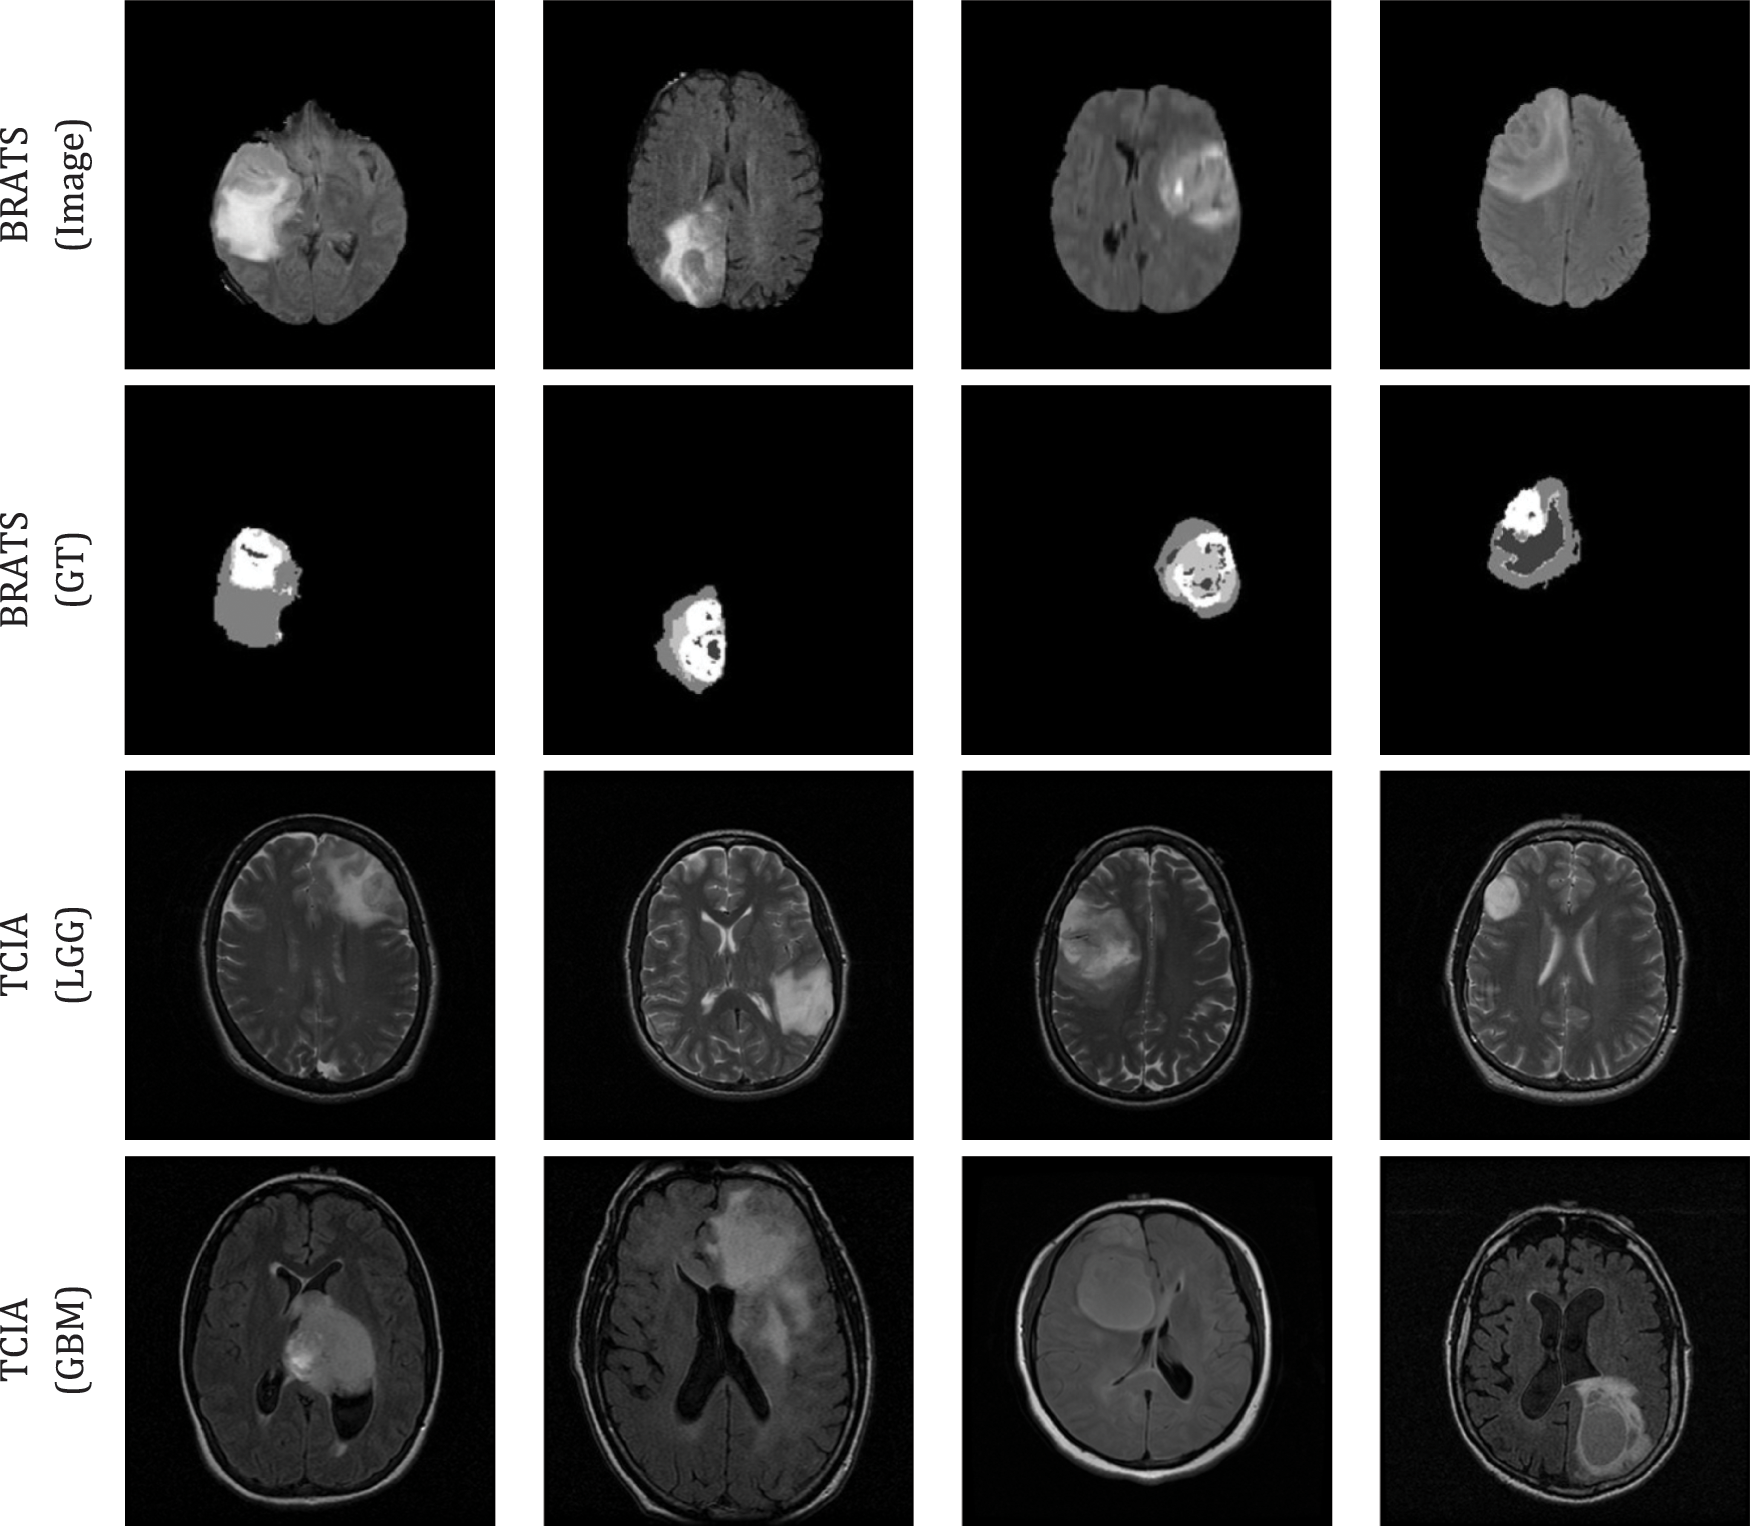

For the experimental evaluation, 4000 numbers of 2D slices (2000 LGG and 2000 HGG images) were considered for the BRATS2015 and 4000 numbers of 2D slices (2000 LGG and 2000 GBM images) were considered from TCIA. Among these images, 70% were considered to train the classifier, 20% to test the classifier and 10% to validate the classifier performance using a 5-fold cross validation. The sample test images of both these databases are depicted in Fig. 3 and Fig. S1 shows sample test images of various MRI modalities collected from BRATS2015.

Figure 3: Sample test images considered in this research